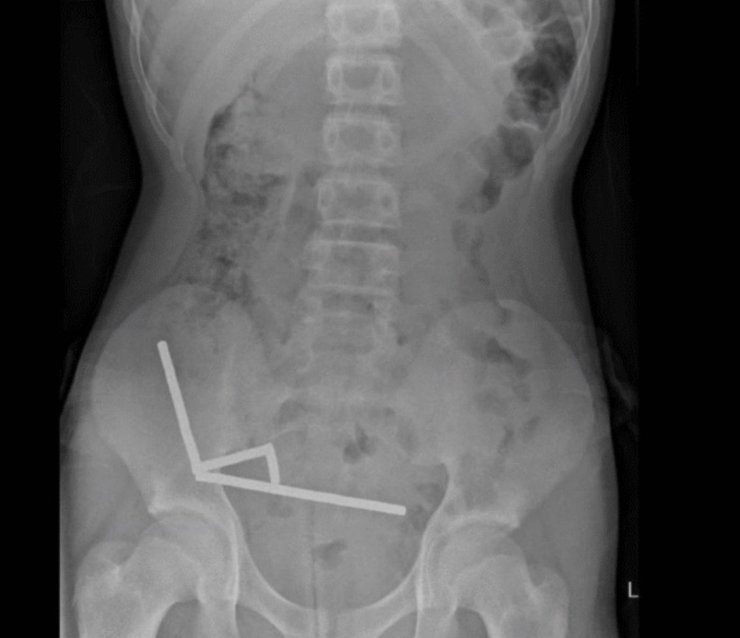

Рентгеновское изображение магнитов в брюшной полости | Фото: ScienceAlert

После того, как врачи сделали рентгеновские снимки брюшной полости подростка, они обнаружили, что в разных отделах кишечника мальчика находятся четыре линейных цепочки из неодимовых магнитов, которые соединились. Мелкие металлические предметы соединились, создав разрушительные последствия.

Рентгеновский снимок, на котором видны цепочки магнитов в брюшной полости новозеландского подростка